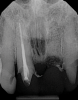

(5.) In a CBCT image axial view, the MB1 and MB2 canals are readily visible in tooth No. 14, and in the coronal view, these two separate canals can be seen to merge into a single apical opening.

Figure 5

Being able to see the number and shape of the canals accurately prior to treatment is the desire of any clinician who performs endodontics. Research suggests that, due to improved diagnostic accuracy, the final treatment plan may change in up to 50% of endodontic cases if CBCT is used rather than traditional 2D imaging.14,15 The question of whether or not a patient has an MB2 canal can be answered prior to opening the access preparation (Figure 4 and Figure 5). Visualizing single canals that bifurcate in the apical or middle third of the root or those that merge to a single apical opening can help clinicians to understand their instrumentation needs in advance. In addition, the ability to measure the length and shape of a canal planned for instrumentation prior to utilizing an apex locator helps to confirm any measurements obtained by other means. It should also be noted that the ability to see a pathosis in 3 dimensions and to involve the patient in understanding his or her condition prior to any decision-making allows for definitive treatment planning. In fact, many patients have pathoses associated with teeth that are asymptomatic that remain unknown to them until they are visually presented with the evidence (Figure 6).